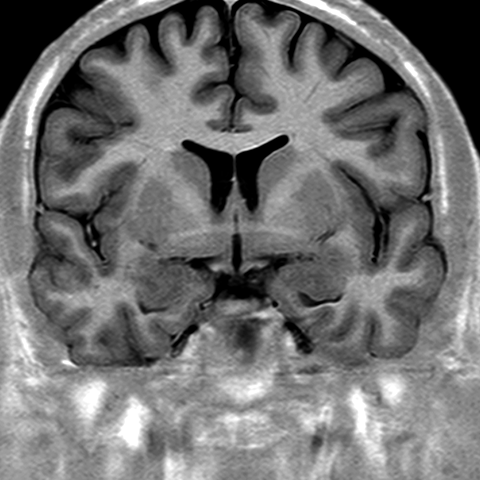

Cerebral Hemispheres, MR (normal) [7 of 9]